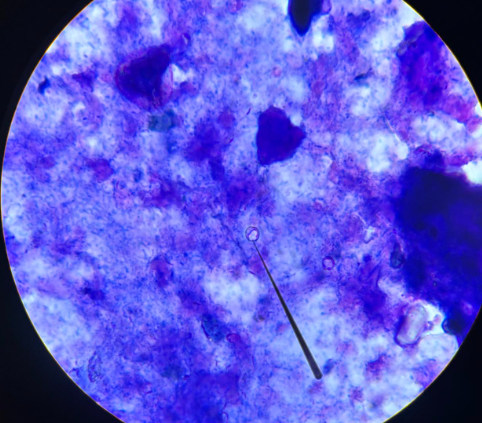

balantidium coli trofozoity